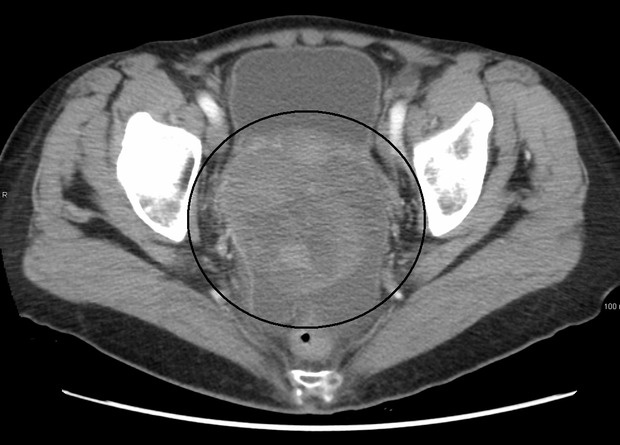

Заболеваемость раком яичников составляет 10,9 на 100000 женщин из общей популяции в год. Среди раков гинекологической сферы у рака яичников самая большая смертность (6,7 женщин на 100000 всех женщин в год). Заболевание характерно в первую очередь для женщин после менопаузы (средний возраст 63 года) и часто возникает у нерожавших, а также у тех, кто принимает эстрогены после климакса. Если в семье были случаи рака яичников, груди или толстой кишки, то это тоже влияет на предрасположенность к заболеванию. Факторы риска есть у многих женщин, но не у всех развивается рак, а у некоторых женщин без факторов риска он, наоборот, развивается. Медицина пока не может точно предугадать возникновение рака, поэтому пытается выявить его на ранних стадиях, основываясь на симптомах, онкомаркерах и ультразвуковом исследовании.